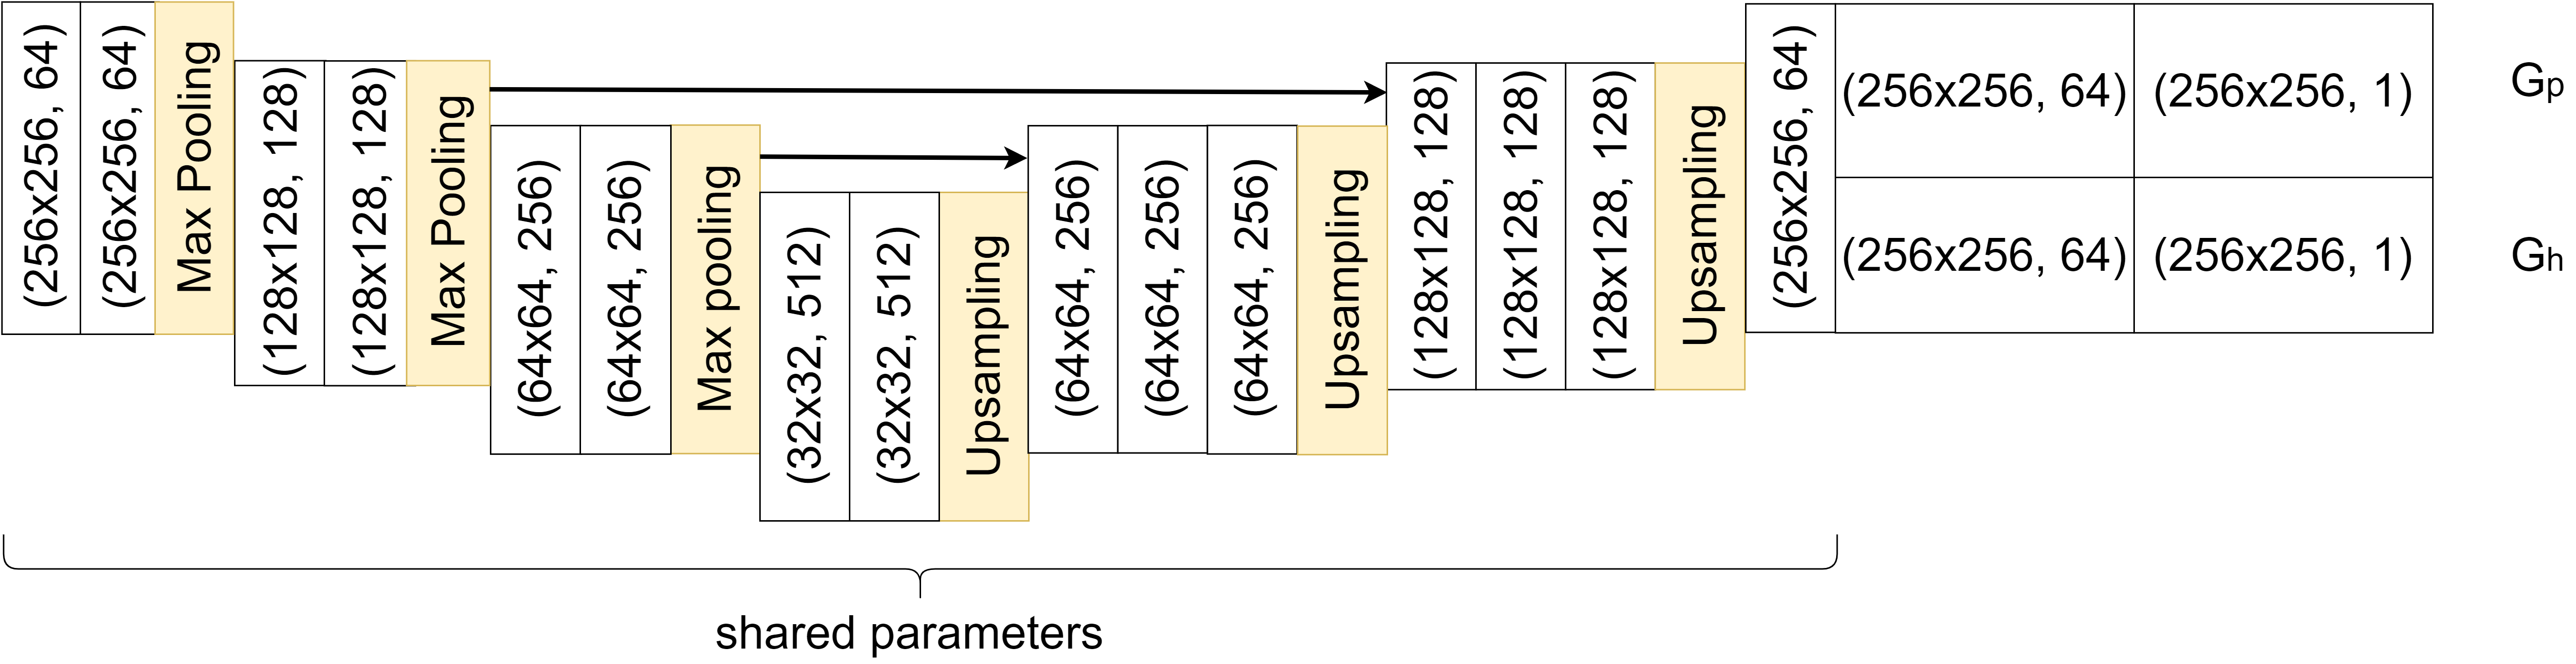

The generator consists of two branches, its architecture is shown in Figure 2. We refer to the generator for generating images of class and generator for generating images of class .

The skip connections of the generator ensure that the artificial image maintains the detailed structures of the input image. This is a way to alter only the necessary features, thus making the difference map more accurate. The skip connection in the uppermost layer turned out to be too restrictive to perform the translation to another class. By omitting this skip connection, we enable the generator to perform structural changes.

The discriminator network has the task to both classify images into healthy and diseased subjects and to distinguish between real and artificial images. Therefore, it consists of three subnets that share parameters, as shown in Figure 3. distinguishes between real and artificial images of class , does the same for class and is the network for classification, following the structure of a VGG net [22]. The branching of the generator and discriminator gives a higher range of flexibility compared to StarGAN, which turned out to be beneficial for image-to-image translation.